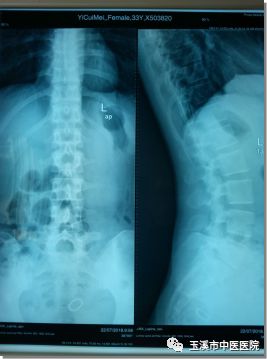

矣某某,女,33歲,因“反復(fù)腰痛4年,加重伴左側(cè)腰臀部麻痛1周”入院,入院后腰椎MRI提示:腰5/骶1椎間盤在左后方突出明顯,腰5/骶1椎間盤層面椎管狹窄。診斷為腰5/骶1椎間盤脫出(巨大型),經(jīng)過(guò)骨傷II科醫(yī)療團(tuán)隊(duì)充分討論,綜合考慮患者的其它情況,決定采用當(dāng)前最先進(jìn)的椎間孔鏡微創(chuàng)手術(shù)為這位年輕的患者治療。在醫(yī)護(hù)人員的精誠(chéng)合作及努力下,歷時(shí)45分鐘成功為該患者進(jìn)行了椎間孔鏡手術(shù),術(shù)后患者當(dāng)即感腰痛及左側(cè)腰臀部麻痛不適癥狀明顯患者,現(xiàn)患者術(shù)后恢復(fù)良好。

術(shù)前影像資料